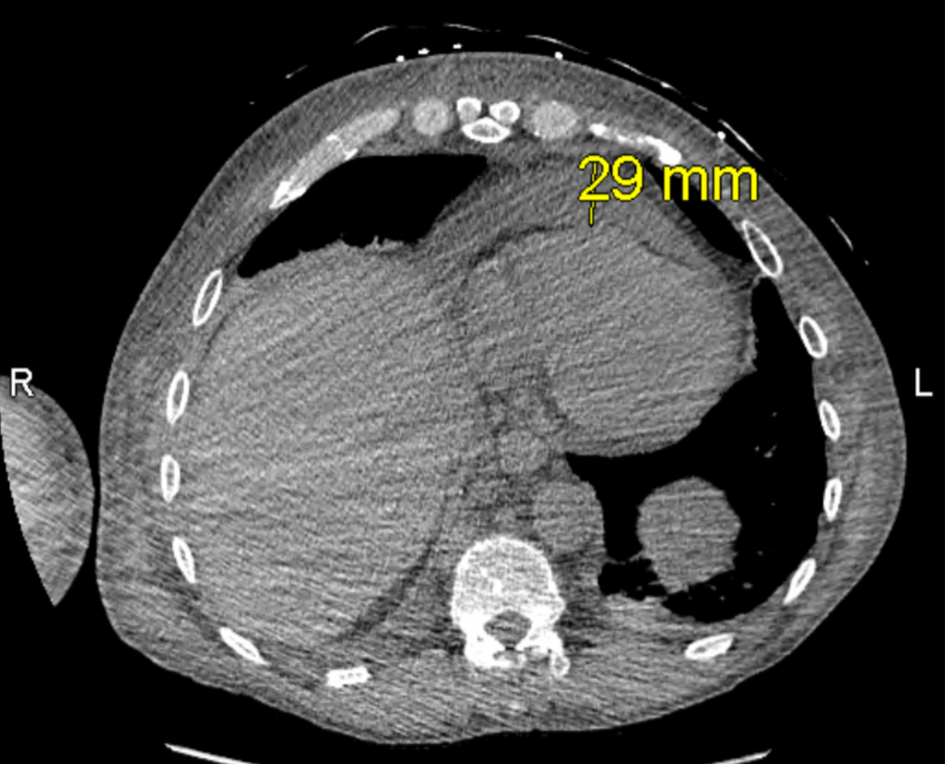

Once admitted, cardiothoracic surgery was consulted and concluded that there were no surgical options for the patient. As the patient’s symptoms progressed, a thoracentesis was performed as well as the initiation of radiation therapy to help reduce the mediastinal mass for suspected SVC syndrome. Additional imaging revealed a 13 × 16 mm mass laterally in the right upper lobe with irregular margins and extension to the pleura laterally (Fig. 2), increase in right pleural effusion, decrease in left pleural effusion, increase in pericardial effusion (Fig. 3), and right upper lobe ground-glass opacities, consistent with pneumonia or atelectasis.

Click for large image

Figure 3. Computed tomography (CT) ion scan of the chest obtained on hospital day 4, depicting pericardial effusion.